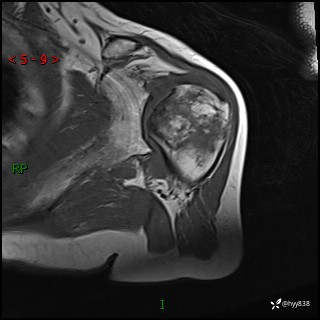

肱骨MRI平扫(axi T1WI+cor T2WI-fs)+CE-fs(COR+SAG)

现病史:患者1月前无明显诱因出现左肩关节疼痛,于2024.07.31就诊于我院骨科门诊完善左肩关节MR:左肱骨头信号异常,肿瘤?建议进一步检查。左肩关节积液。左腋窝淋巴结增大。今为求明确诊断就诊我科,门诊以“骨质破坏”收入我科。 起病以来,精神食欲睡眠尚可,大小便正常,体力体重无明显变化。